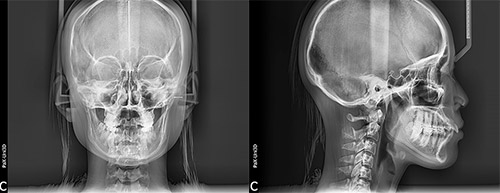

当院では、一定の規格に基づいて頭部や顔を正面・側面から撮影できる「セファログラム」(頭部X線規格写真撮影装置)を導入しています。顎の大きさ・形やズレ、歯の傾斜、口元のバランスなどを把握できる装置で、経時的に撮影することで、骨格の成長の変化や歯の移動を観察できます。